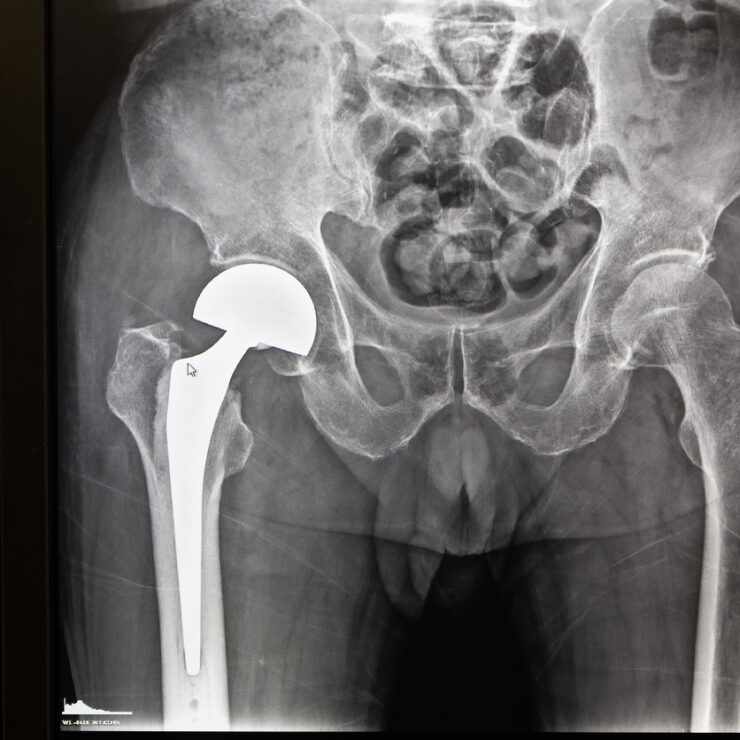

Traitement de l’arthrose de hanche par prothèse totale

Changement de prothèse totale de hanche